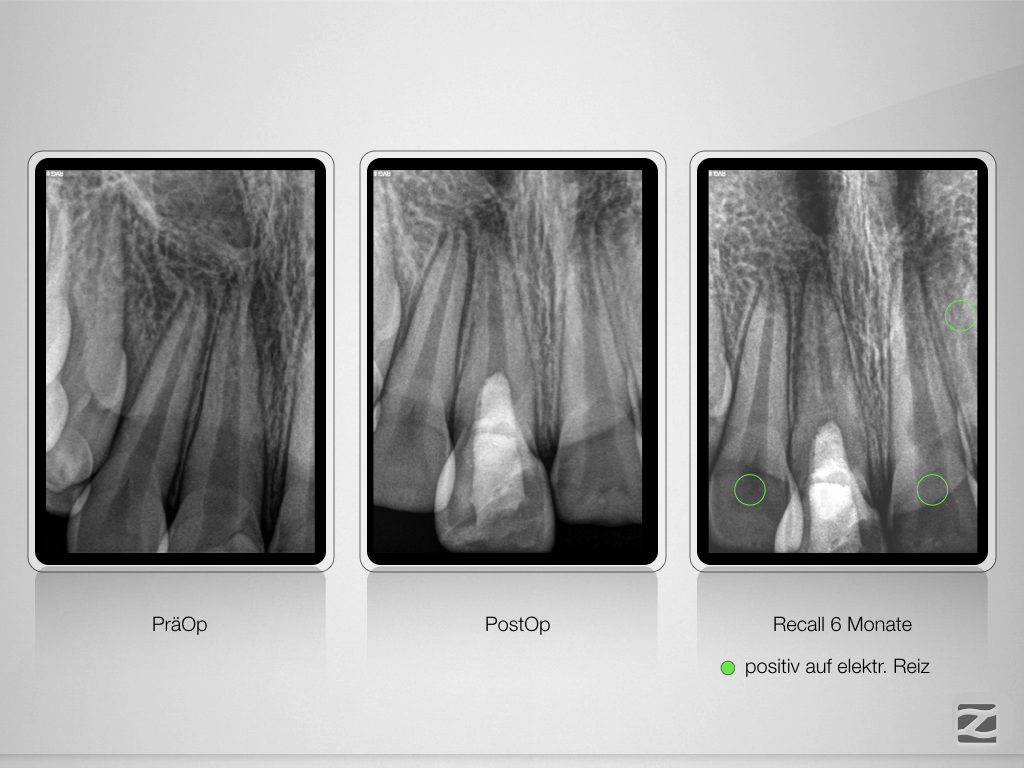

And the show goes on-Trauma, die Zweite.